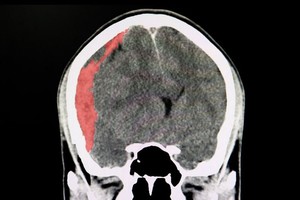

La recuperación de Diego Maradona tras la operación de un hematoma subdural que se le practicó este martes por la en la Clínica Olivos "es buenísima", aseguró este miércoles por la tarde su médico personal, Leopoldo Luque, en las puertas del centro de salud donde el astro futbolístico se encuentra internado en terapia intensiva.